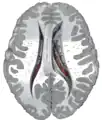

Transverse Cut of Brain (Horizontal Section), basal ganglia is blue | |